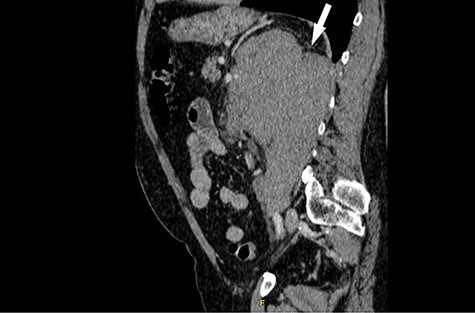

His CT scan identified large left renal tumour invading psoas muscle. Left mid ureteric tumour as well. Multiple regional nodes. No hepatic, pulmonary or osseous metastasis. The scan was highly suggestive of metastatic transitional cell carcinoma (Figs. 1 and 2).

Computed tomography (CT) revealing a large insinuating left renal soft tissue mass measuring 140 × 105 mm.

Computed tomography (CT) sagittal section showing predominant bulk of the mass is extrarenal that posteriorly breaches the fascia to involve the diaphragm and psoas muscle. Medially it reaches the intervertebral foramen.